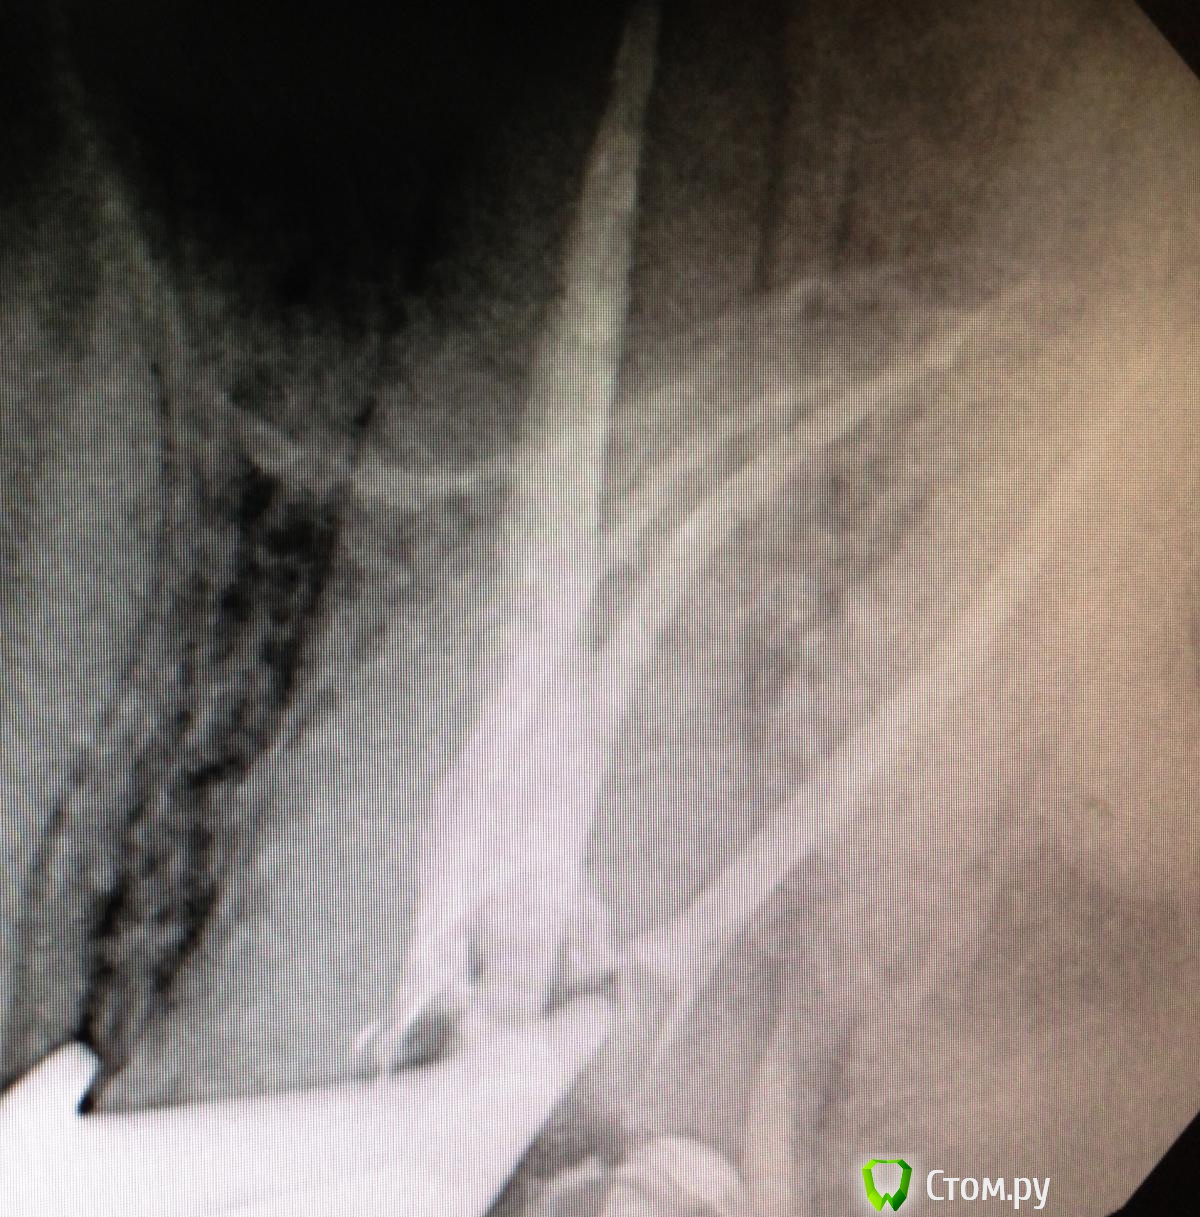

SSTi Опубликовано 22 ноября, 2014 Автор Поделиться Опубликовано 22 ноября, 2014 26. Хронический апикальный периодонтит. Пропущенный мб2. Зуб лечили год назад в гсп. Платно. И весь год он болел. Постоянные слабые боли. Переуссия +. 1 визит - коффердам, доступ, распломбировка мб, дб, небного. Поиск мб2. Обработка 4 каналов - протейпер д2,д3, профайлы - небный до 45.04. , мб и дб до 35.04, мб2 до 30.04. Гипохлорит, эдта, хлоргексидин, уз. Кальций. 2 часа. Второй визит - болей нет. Переуссия б/б. Вымыли кальций, еще моемся долго, латералка ( ан+ ). 2 часа. Ссылка на комментарий